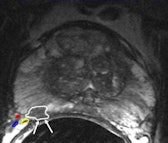

A 48-year-old sexually active male with PSA 9; TRUS biopsy Gleason 4+3 PC at right PZ; stage T1c. Nerve-sparing prostatectomy was performed showing submillimeter ECE and negative resection margins. Postsurgery patient was potent and continent. Left: Axial T2-weighted MR image shows low signal tumor in right PZ (white area) with obliteration of the white fat at the rectoprostatic angle (arrows), indicating minimal ECE = PI-RADS 5. The NVB is indicated by red, blue, and yellow. Right: Nerve-sparing prostatectomy showed Gleason 4+3 PC with submillimeter ECE (T; blue area) at right PZ. Resection margins were negative. Patient was potent after surgery.

A 48-year-old sexually active male with PSA 9; TRUS biopsy Gleason 4+3 PC at right PZ; stage T1c. Nerve-sparing prostatectomy was performed showing submillimeter ECE and negative resection margins. Postsurgery patient was potent and continent. Left: Axial T2-weighted MR image shows low signal tumor in right PZ (white area) with obliteration of the white fat at the rectoprostatic angle (arrows), indicating minimal ECE = PI-RADS 5. The NVB is indicated by red, blue, and yellow. Right: Nerve-sparing prostatectomy showed Gleason 4+3 PC with submillimeter ECE (T; blue area) at right PZ. Resection margins were negative. Patient was potent after surgery.One in six men in their lifetime will be clinically diagnosed with prostate cancer, and this accounts for 350,000 cases, annually or 25% of all new male malignancies diagnosed in Europe, the authors noted. Currently, digital rectal examination, serum prostate specific antigen (PSA) -- a nonspecific blood test -- and transrectal ultrasound-guided biopsy -- where the target is mostly invisible -- are used as diagnostic tools.